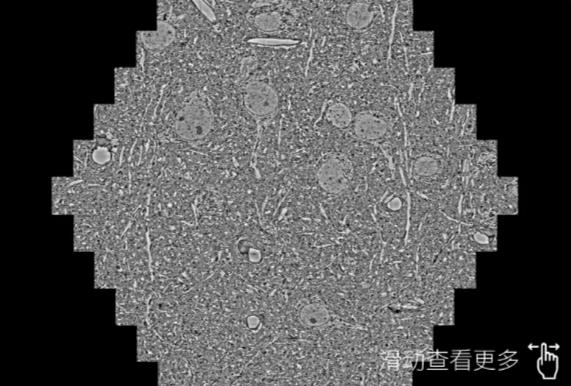

鼠脑切片。左图使用庆阳蔡司庆阳扫描电镜MultiSEM706对165μmx143pm面积区域成像,耗时仅需1.5秒。右图为鼠脑切片中30μm区域放大效果。样品由芝加哥大学B.Kasthuri提供。

使用蔡司高速庆阳扫描电镜MultiSEM对1mm²人脑皮层组织进行高分辨成像,并对其中的各种细胞结构进行三维重构分析。左图展示了2x3mm²组织平面中锥体神经元的三维重构效果。右图显示了局部体积神经元三维重构。图像由哈佛大学chtman实验室提供,渲染图由D. Berger 制作。